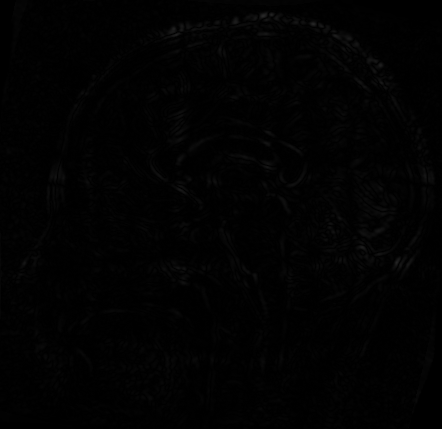

配准前后初始化点的位置

运行改进后的配准方法代码,对同样的脑部图像进行配准,并于改进前的方法进行比较,如下图所示,可以看到改进后配准的收敛速度快了不少。